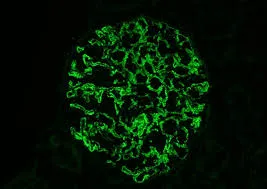

Amiloidose renal: aspectos sobre patogenia, diagnóstico e proteomica

Amiloidose renal: aspectos sobre patogenia, diagnóstico e proteomica

Este vídeo apresenta, de forma didática e baseada em evidências, os principais achados da tese de doutorado sobre amiloidose renal, com foco em proteômica glomerular e ativação do complemento. São discutidos aspectos diagnósticos, implicações fisiopatológicas e correlações clínico-patológicas relevantes para a prática do nefrologista. O conteúdo sintetiza dados inéditos de matriz extracelular glomerular e diferencia perfis entre subtipos de amiloidose. Trata-se de um material aprofundado e acessível, ideal para atualização de especialistas na área.